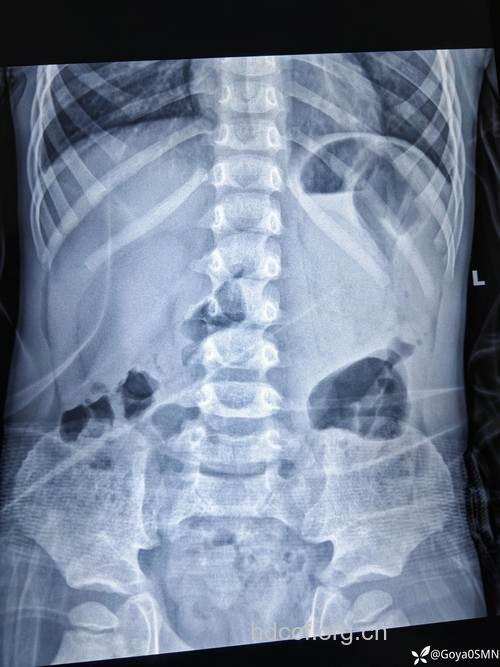

目前用X线检查胃,通常采用两种方法,单纯钡餐检查和气钡双重对比检查,后者一般来说优于前者。 所谓气钡双重对比检查,是指让患者先喝钡剂观察胃的情况,然后,嘱患者服一定数量的发泡剂,使胃腔内充气。,再次观察胃腔情况。经过此2种情况对比,得出初步诊断。